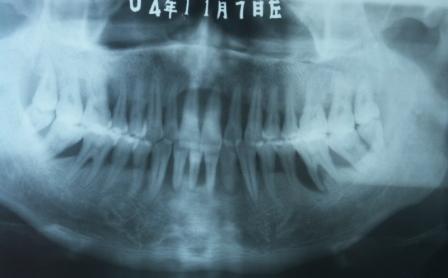

牙周炎X线片

读片------

牙周

炎患者的X线片